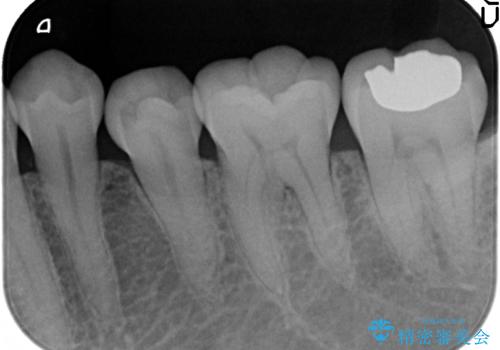

- 右下の奥歯が冷たいものを飲むとしみるので診て欲しいといらっしゃった方の症例です。

古い樹脂を除去し、PGA(ゴールド)インレーによる修復を行いました。

虫歯治療は虫歯の進行度によって処置が変わってきます。

虫歯が小さければ、インレー・クラウン等による修復・補綴処置を行うだけで済みます。

しかし虫歯が大きくなると神経処置や抜歯等をしなければならない場合もあります。

ですので虫歯治療においては早期発見・早期治療が肝要です。